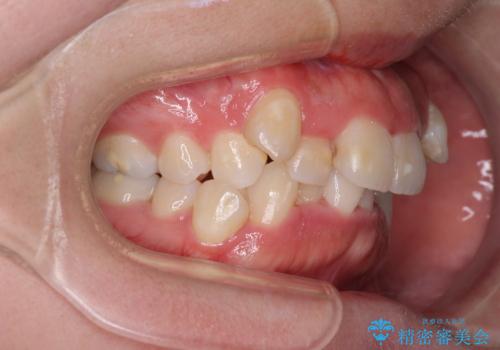

- 上下の八重歯やデコボコを気にして来院された患者様です。

上下ともに八重歯が顕著であったので、上下左右第一小臼歯4本を抜歯し、補助装置を使用して速やかに改善しながら、ワイヤー装置にて矯正治療を行うこととしました。

気になっていた八重歯は装置装着から3か月ほどで解消されました。

2年以内を目標として治療を開始しましたが、1年半ほどで終えることができました。